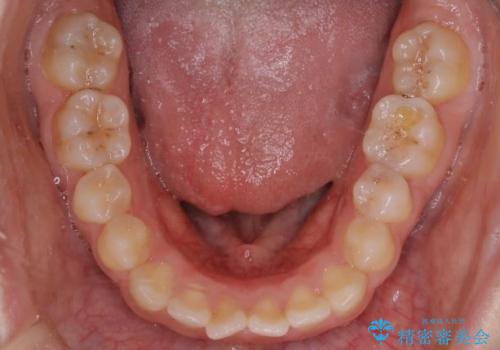

前歯のガタツキ、前歯の噛み合わせ(開咬)をインビザライン治療で治しました

- 前歯のがたつき、噛み合わせが気になるとのことで来院された患者様です。

インビザラインを使用して治療しました。

前歯がしっかり噛んでない状態(開咬)を治すために、前歯にゴムをかける必要があります。ゴムかけは患者様にご協力していただきます。